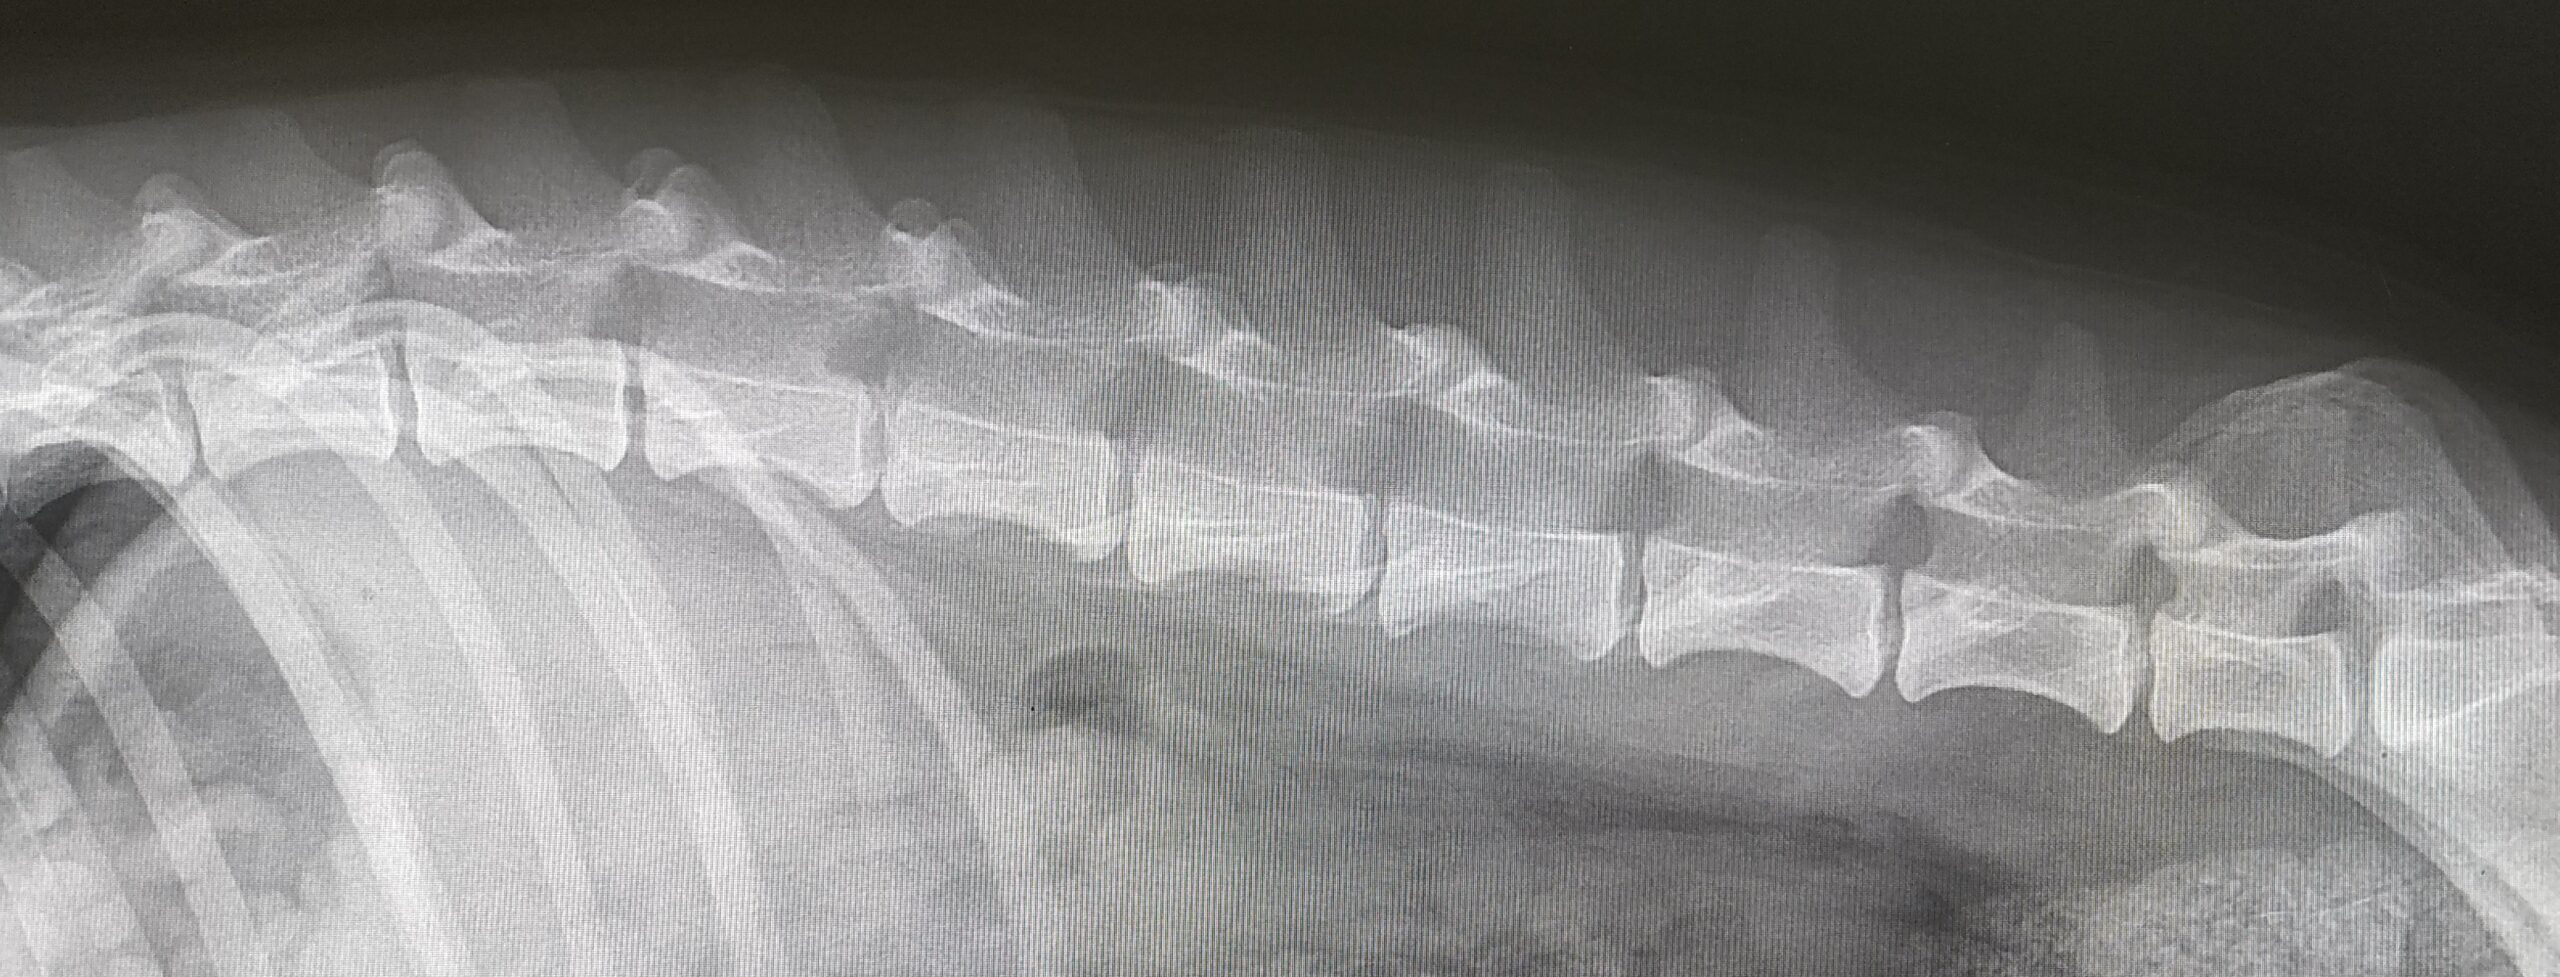

Заболевания позвоночника у домашних животных: диагностика и лечение

Раздел: Визуальные истории